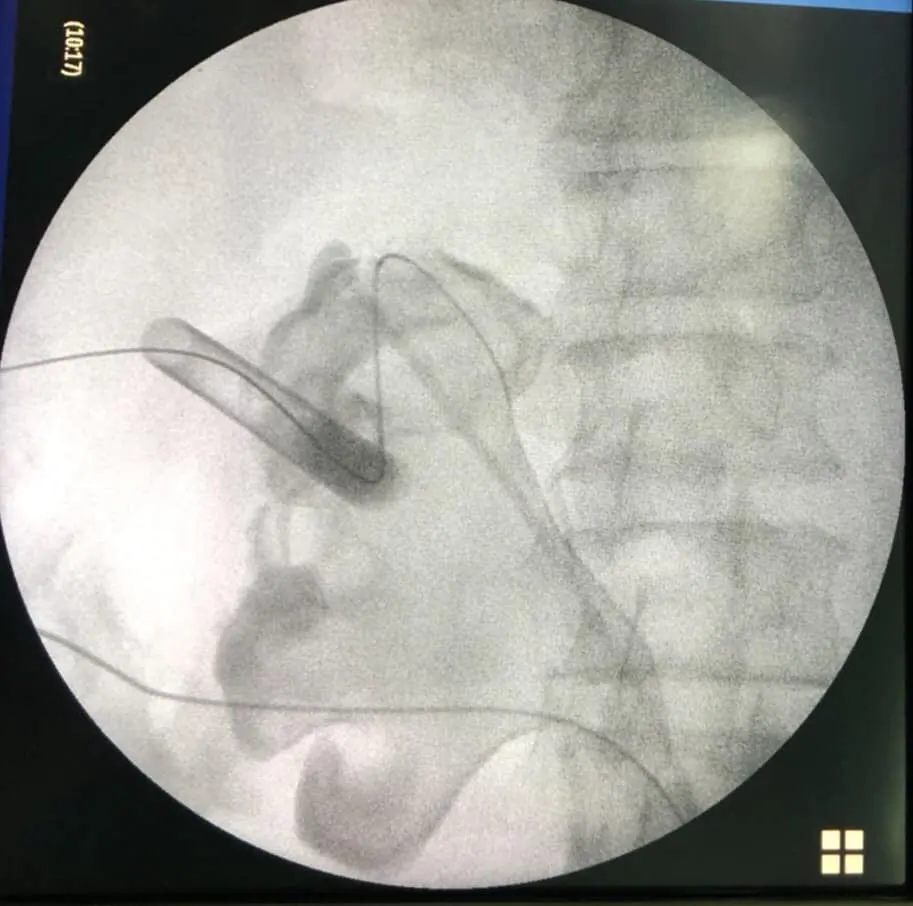

ตะลึง! กองนิ่วที่ผ่าตัดจากคนไข้รายเดียว!!

กองนิ่วที่ได้รับการผ่าตัดจากคนไข้รายเดียว หลังจากที่คนไข้รายนี้ต้องทนทุกข์ทรมานจากอาการปวดหลังและไตเสื่อม สุดตะลึง! เมื่อเข้ารับการผ่าตัดพบว่านิ่วเยอะมาก! จนสามารถนำมาเรียงให้เป็นคำว่านิ่วได้เลย

โดยภาพนี้ถูกโพสท์มาจากเฟซบุ๊กคุณ Sirianan Prasit คุณหมอที่โรงพยาบาลยะลา โดยได้โพสท์ข้อความระบุว่า ของกลางที่พบในคนไข้รายหนึ่ง หลังจากที่ต้องทนทุกข์ทรมานกับอาการปวดหลังและอาการไตเสื่อม

คงไม่ต้องบอกว่า......คืออะไร 😁😁😁 ไม่อยากเป็นนิ่ว โปรดดื่มน้ำวันละ6-8แก้วต่อวันครับ นิ่วในไตใหญ่เบ้อเริ่ม

Uro Yala Team